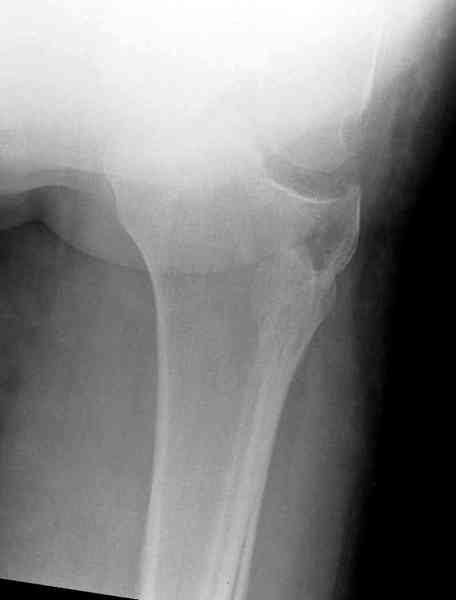

Здравствуйте, уважаемые коллеги!Подскажите, пожалуйста, какой выбрать доступ и способ фиксации при импрессионном переломе заднего отдела наружного мыщелка большеберцовой кости. Женщина 40 лет, травму получила 02.01.2008, катаясь на горных лыжах.Есть ли здесь необходимость использовать задний доступ, или можно справиться через наружный? Есть ли шансы сделать закрыто - под ЭОП через медиальное "окошко" поднять забойником суставную поврехность? Какой лучше использовать фиксатор?Спасибо.

Из медиального окна можно приподнять латеральную

импрессию. Фиксация тремя параллельными шурупами в

эпифизарной части над импрессией. Создается крыша,

которая предупредит коллапс. На образовавшуюся полость - костная пластика из аутокости или синтетический заменитель. Мы применяем Osteoset в 4-5 мм диаметре таблеточки или иньекционную форму Prodens.

Медиально, обычно на протовоположной

строне, делается окно в кортикальном слое, кривым забойником под рентгеном поднимается импрессия.

Это техника применяется, когда имеется

центральная импрессия, а при ипрессии с краевым переломом - после приподнимания импрессии опорная (Butress) пластина, как на снимке.